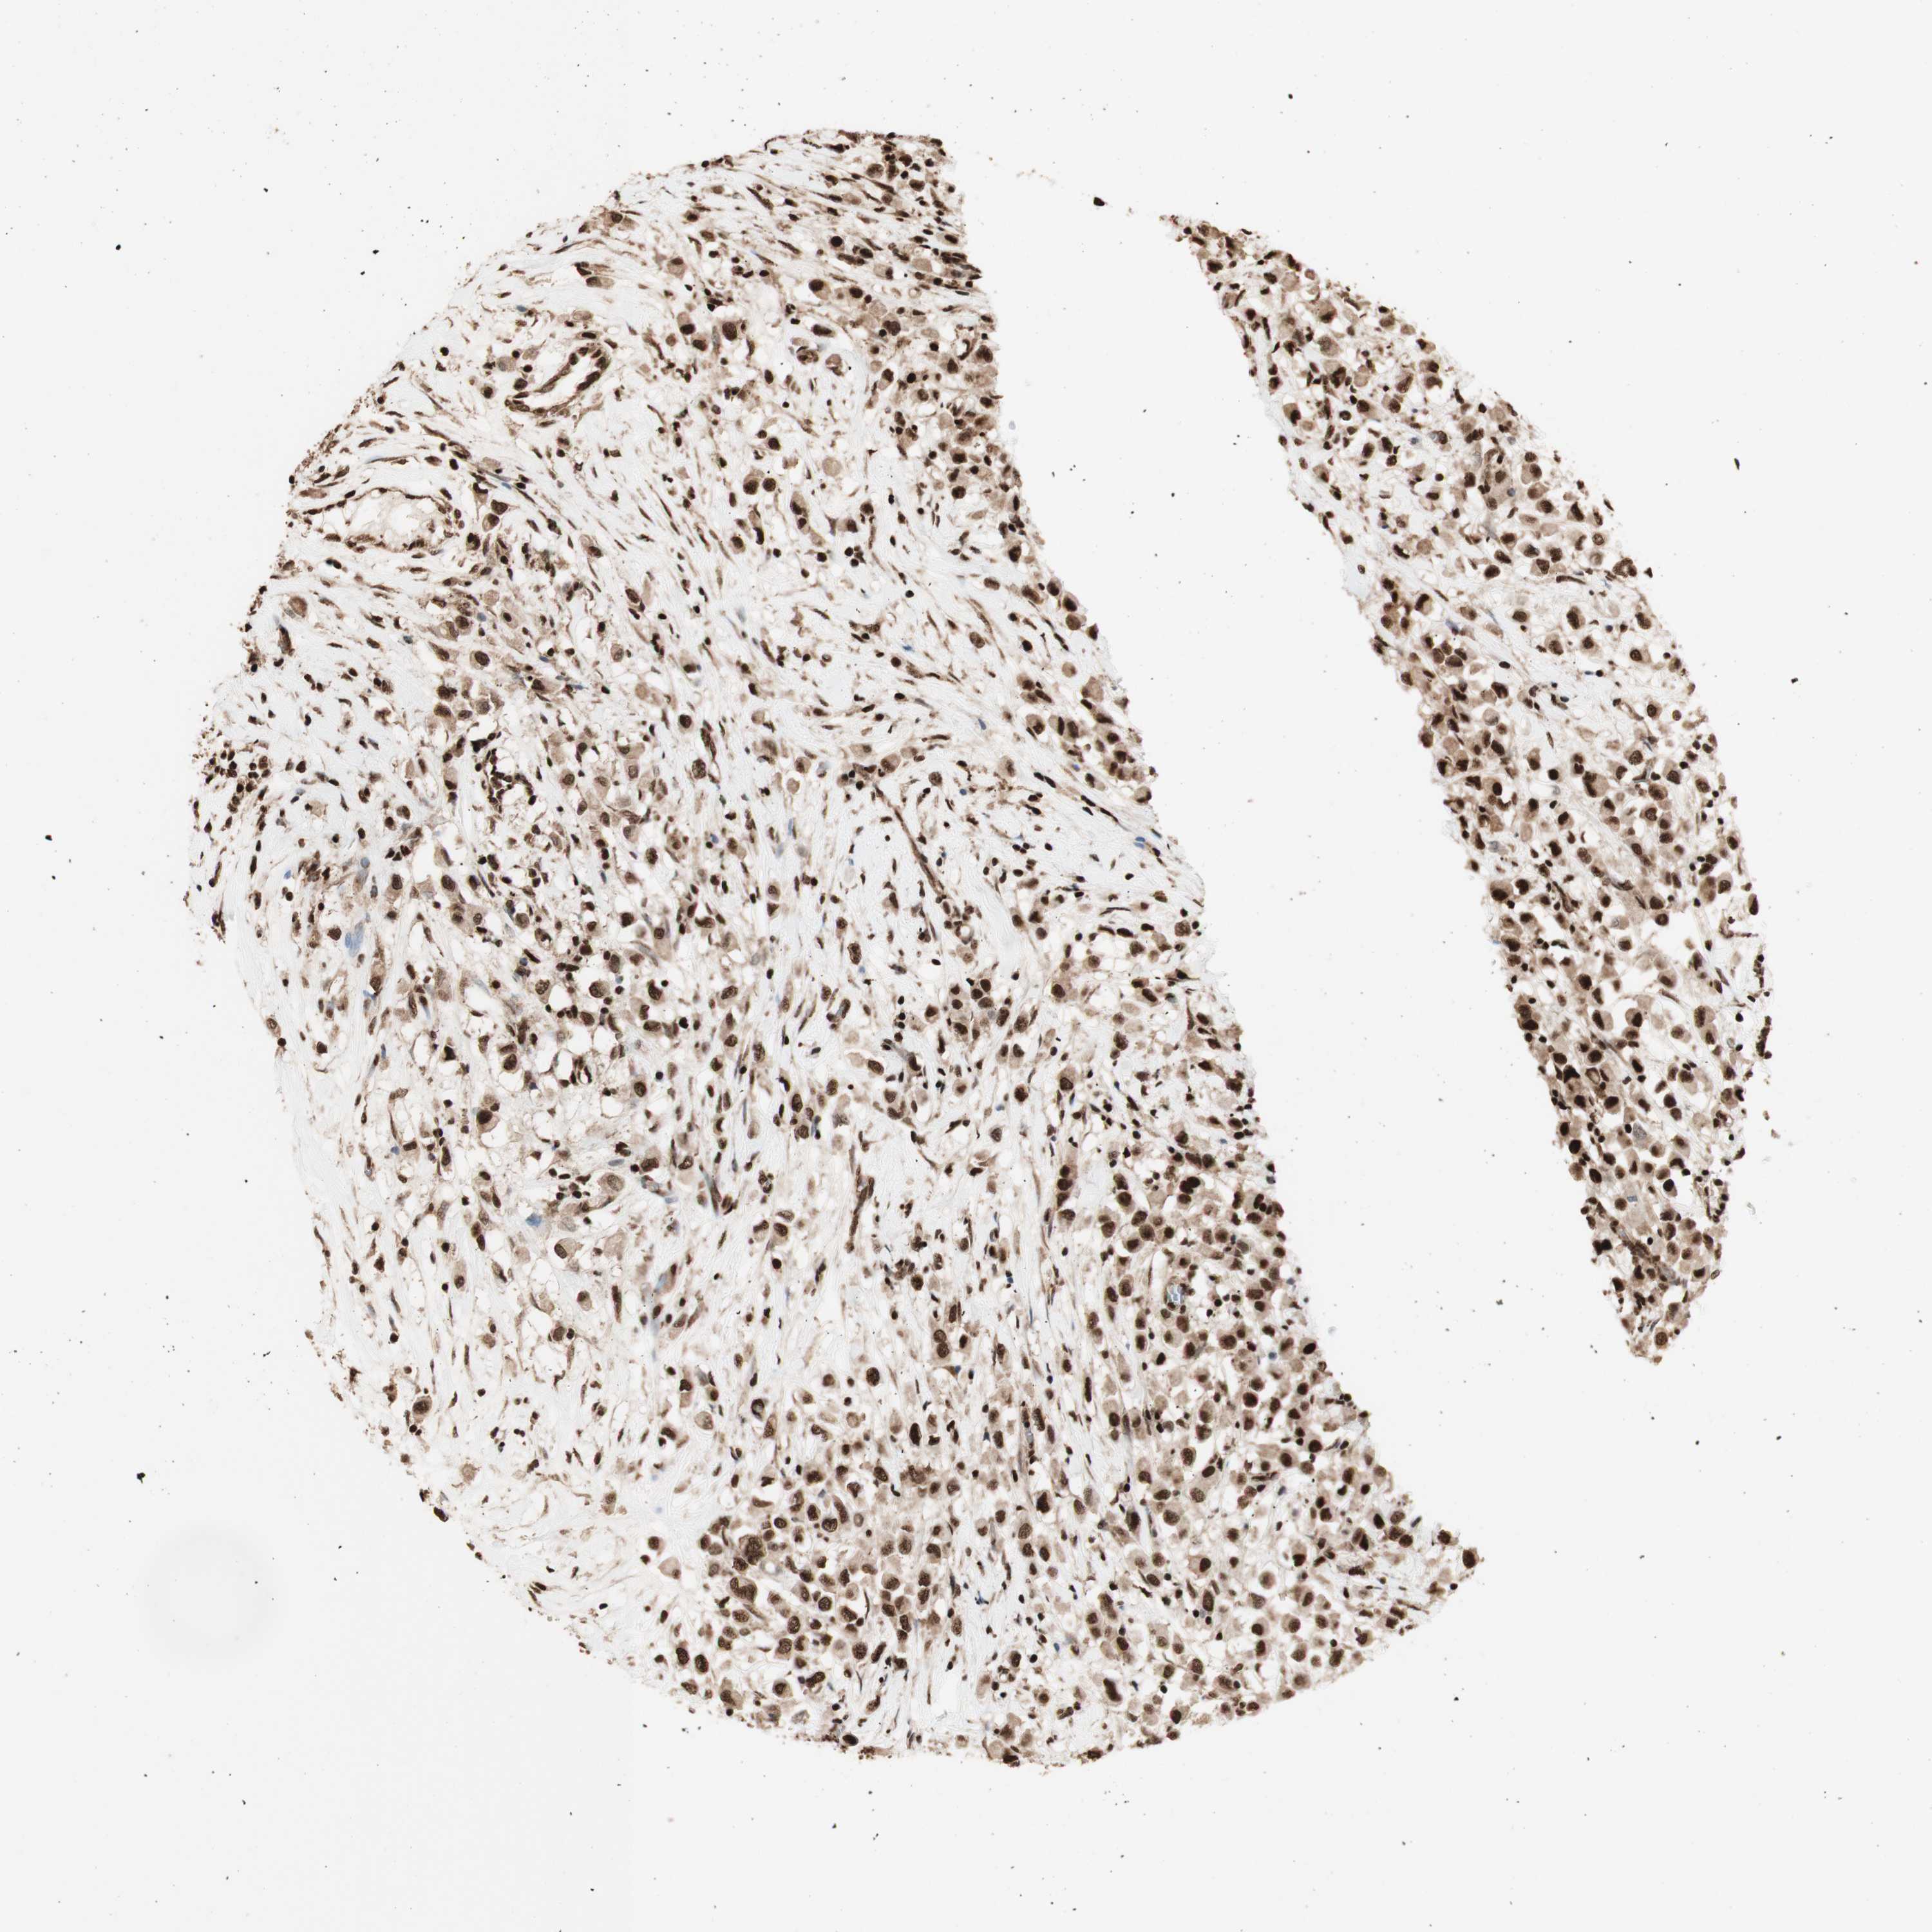

BRCA TCGA BRCA VALIDATION PROTEIN EXPRESSION

ANTIBODIES

AND

VALIDATION